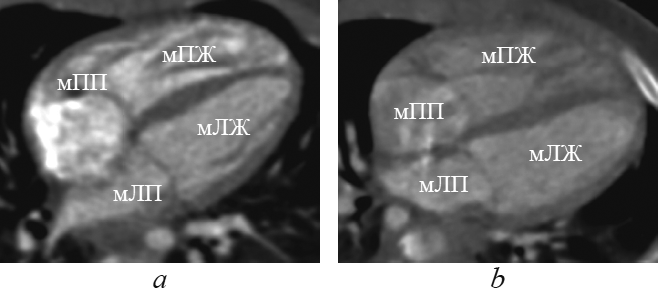

При корригированной транспозиции магистральных артерий морфологически правый желудочек располагается слева и сзади от морфологически левого желудочка (рис. 5, 6).

Рис. 6. Реформация приточных отделов желудочков при корригированной транспозиции магистральных артерий. мЛЖ — морфологически левый желудочек; мЛП — морфологически левое предсердие; мПЖ — морфологически правый желудочек; мПП — морфологически правое предсердие

Fig. 6. Supply ventricles division reformation in corrected great arteries transposition. мЛЖ — morphologically left ventricle; мЛП — morphologically left atrium; мПЖ — morphologically right ventricle; мПП — morphologically right atrium

При обычном расположении морфологически правое предсердие находится справа от морфологически левого предсердия. При обратном расположении морфологически правое предсердие находится слева от морфологически левого предсердия. Положение предсердий почти всегда связано с положением внутренних органов, но не зависит от положения желудочков или магистральных артерий. При транспозиции (см. рис. 4) и корригированной транспозиции (см. рис. 5, 6) взаимное расположение предсердий, как правило, обычное.